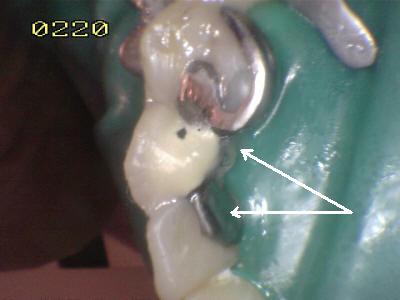

Cementado con la goma dique.

Observe los excesos de cemento de resina de curado dual (flechas

blancas)